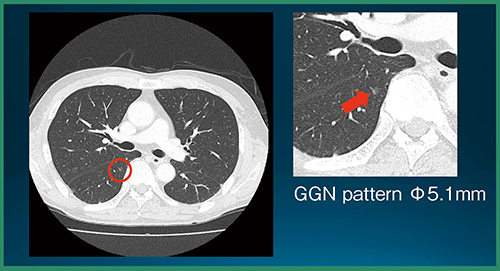

肺結節CADeのプロトタイプは,対象データを開いた時点で,すでに肺結節の検出は完了しており,結果を表示する前に全画像の確認を促すアラートが表示される。検出結果を表示すると,スライス位置を示すインジケーターにも結節が検出された位置が示され,各スライスに直接飛ぶことができる。検出された肺結節は,画像上で縁取りされ,計測結果も表示される(図1)。また,画面内に別ビューアを立ち上げてMPR画像で結節を詳細に確認することができる(図2)。読影者はこれらの情報を参照し,各結節についてフォロー対象とするかを判断することになる。

図1 肺結節CADeプロトタイプの結果表示

読影実験の結果,CADe単体の検出率は89.2%(66/74結節),未検出数は0.27個/症例,結節以外の誤検出数は0.73個/症例であった。また,統計解析の結果,評価者全員の平均FOM(figure of merit)は,CADeあり読影で有意に向上した(p=0.0009)(図3)。図4は,評価者は指摘せず,CADeが指摘した症例である。非常に淡いすりガラス状陰影であるが,背景肺に問題がなければCADeでの検出が可能である。また,図5は,評価者もCADeも指摘しなかった症例で,ごく淡い結節は検出が難しかった。

図4 CADeのみで指摘された症例